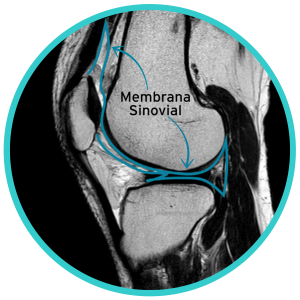

Las articulaciones  sinoviales, incluida la rodilla, recubierta  en su interior por un tejido especializado llamado membrana sinovial, que tiene como función primordial producir el líquido sinovial, encargado entre otras cosas de lubricar las superficies articulares. Además, contiene algunas células encargadas de eliminar desechos del espacio articular.

Es una sustancia producida por las células de la membrana sinovial, rico en ácido hialurónico, una proteína llamada lubricina y un filtrado del plasma. Su color normal es amarillo “pajizo”, debe ser translúcido, con una viscosidad similar a la clara de huevo. Tiene muy pocas células blancas y ocasionalmente pueden encontrarse algunos glóbulos rojos, especialmente si al tomar la muestra se produjo algún traumatismo de un vaso sanguíneo. NUNCA deben encontrarse bacterias.